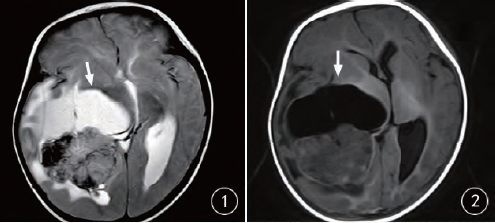

摘要:橫紋肌樣瘤最新治療技術(shù)為小巷深處的生命之光,帶來了新的希望。通過采用最新的治療技術(shù)和方法,醫(yī)生們能夠更有效地應(yīng)對橫紋肌樣瘤,提高患者的生存率和生活質(zhì)量。這些新技術(shù)包括先進(jìn)的手術(shù)方法、藥物治療和放射治療等,為患者提供了更多的治療選擇和更好的治療效果。

橫紋肌樣瘤是一種罕見的腫瘤,但生命綠洲卻憑借其獨(dú)特的醫(yī)療視角和先進(jìn)的設(shè)備,走在治療的前沿,這里采用的治療技術(shù)不僅結(jié)合了傳統(tǒng)手術(shù)的優(yōu)勢,還融入了最新的生物技術(shù)、基因療法和免疫治療等前沿科技,經(jīng)驗(yàn)豐富的醫(yī)療團(tuán)隊(duì)緊跟國際醫(yī)學(xué)的最新進(jìn)展,不斷嘗試將最新的研究成果應(yīng)用到臨床實(shí)踐中。